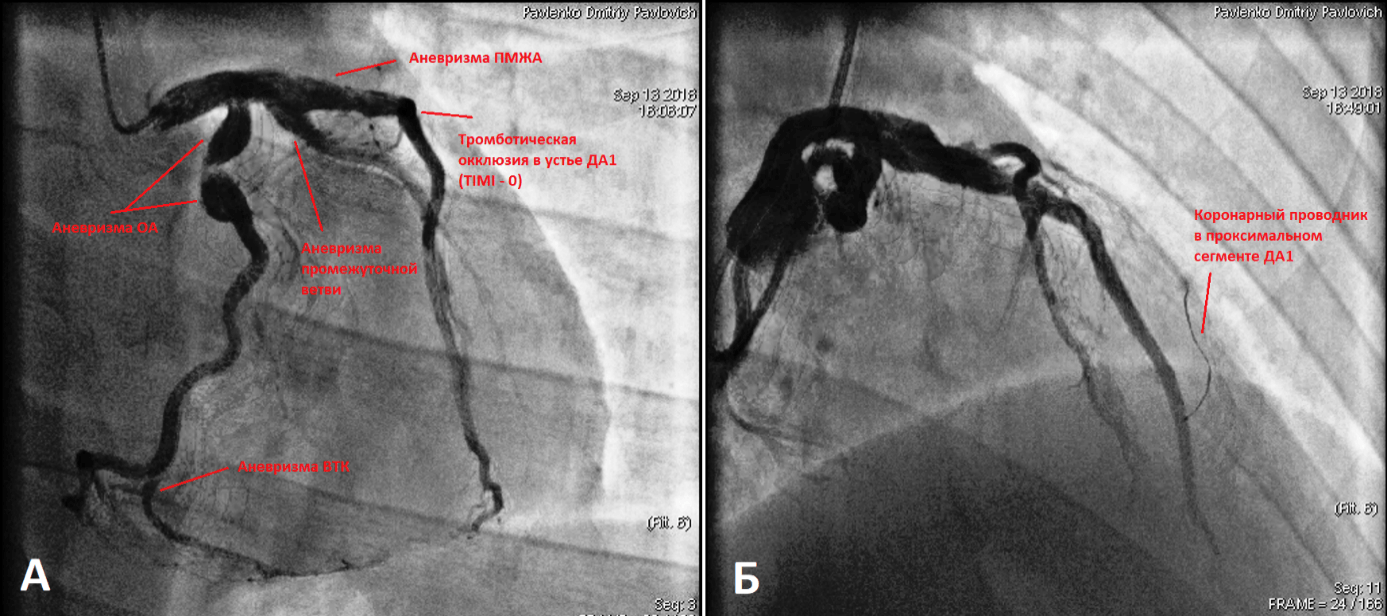

При поступлении в Военно-медицинскую академию им. С.М. Кирова при объективном обследовании, за исключением ослабления первого тона на верхушке сердца, других патологических изменений выявлено не было. Результаты клинических анализов крови и мочи были в пределах нормы. В лёгочной ткани очаговых и инфильтративных изменений не наблюдалось, корни лёгких были чёткие и структурные, синусы свободные, тень сердца не расширена. ЭКГ соответствовала переходу острейшей ЭКГ-стадии проникающего инфаркта миокарда в области передней и боковой стенок левого желудочка в острую (рис. 1). По данным биохимического исследования крови: тропонин-Т – 8,06 нг/мл, КФК – 2490 МЕ/л, КФК-МБ – 196,28 МЕ/л. При эхокардиографическом исследовании наблюдалось уплотнение стенок аорты, камеры сердца были нормальных размеров, клапанный аппарат без особенностей. Расчётное давление в лёгочной артерии в пределах нормы. На фоне сохранённой общей сократительной функции левого желудочка (60% по Simpson) были выявлены зоны акинезии в средних и верхушечных сегментах его передней и боковой стенок. На основании полученных данных был установлен диагноз: «Острый проникающий инфаркт миокарда в области передней и боковой стенок левого желудочка» и принято решение о необходимости проведения рентгенэндоваскулярной диагностики и лечения острого инфаркта миокарда (рис. 2, 3 и 4).

При коронароангиографии были выявлены множественные АКА: в проксимальном сегменте ОА, в проксимальном сегменте ПМЖВ, проксимальном сегменте промежуточной ветви ЛКА и в проксимальном сегменте ветви тупого края (ВТК). Кроме того, в устье 1 диагональной артерии (ДА), которое тоже имело небольшое аневризматическое расширение, была выявлена тромботическая окклюзия (рис. 2 и 4). Пациенту была выполнена реканализация коронарным проводником PT2 MC, который был доставлен в дистальный участок артерии. По коронарному проводнику заведен аспирационный катетер Export Advance. Выполнена тромбоаспирация с получением тромботические масс из 1 ДА и установлен стент с лекарственным покрытием Promus Element Plus 3,5×28 мм. При контрольной коронароангиографии кровоток в месте установки стента удовлетворительный (рис. 3), участков резидуального стеноза и диссекции не выявлено. На ЭКГ, зарегистрированной после чрескожного коронарного вмешательства, отмечалась ускоренная динамика проникающего инфаркта миокарда в области передней и боковой стенок левого желудочка. На фоне проводимой консервативной терапии состояние пациента улучшилось, и он был направлен на медицинскую реабилитацию в санаторий с последующим освидетельствованием для определения категории годности к военной службе.